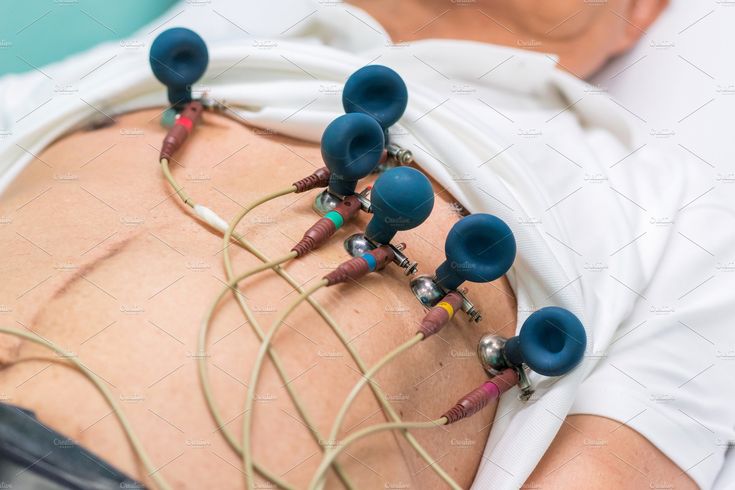

ECG

- ECG facility for heart health monitoring

- Quick and non-invasive testing process

- Helps detect cardiac conditions early

- Supports overall patient evaluation

- Safe and efficient diagnostic service